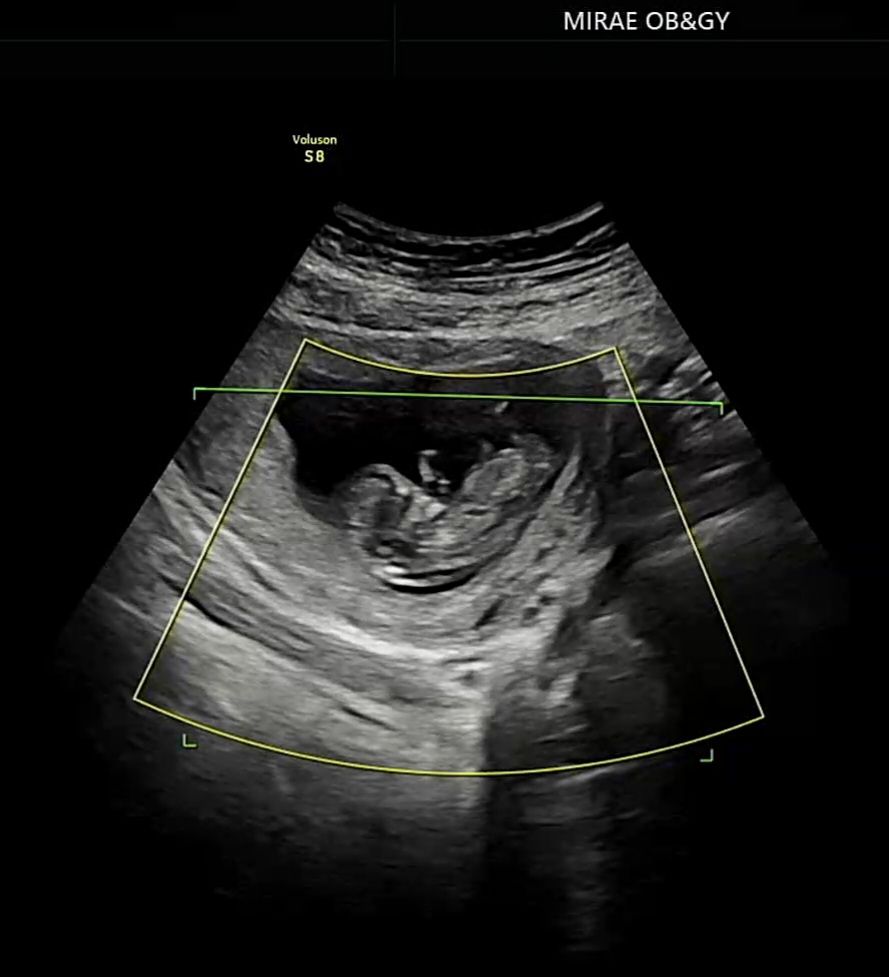

12주차 오늘 산부인과 갔다왔는데 초음파 각도법좀 봐주세용!!고수님들 잘봐주신다는데 저는 아들인지 딸인지 하나도 모르겠어요

지금 시기쯤 성별이 궁금한건 누구나 다 그럴겁니다. 각도법은 12주에서 14주사이에 꼬리뼈가들어가고 생식기가 발달하면서 생기는 하체의 각도로 보는거라서 당연히 지금 시기에 궁금하니 물어보실수도 있죠. 제가 보기엔 아직 허리랑 머리가 많이 말려있고 자세로 봐서는 아기가 아직 많이 쪼그리고 있고 많이 움직였거나 여러 이유로 초음파가 잘 찍히지 않은거같아요. 굳이굳이 눈을 크게뜨고 보자면 저는 아들에 한표 드리고싶네요. 그리고 이거는 제가 병원에 안좋은 기억이 있어서 고민하다가 조심스럽게 말씀드리는건데 혹시 대구지역이신지... 실례가 안된다면 제가 알 수 있을까요...?

각도법을 보려면 생식기부위가 보여야하는데 지금 영상샷 자체가 위상차때문에 잘 안보이네요 ㅠㅠ

사진 다시 바꿧는데 보이시나요?ㅜ

아니요 ㅠ 다른 각도법 사진 보시면 아실거에요. 생식기 부위가 확실히 보여야해요 ㅠ

저도 잘모르겠네요 사진을 어떻게 줘야할지 어디가 생식기 부위인지...